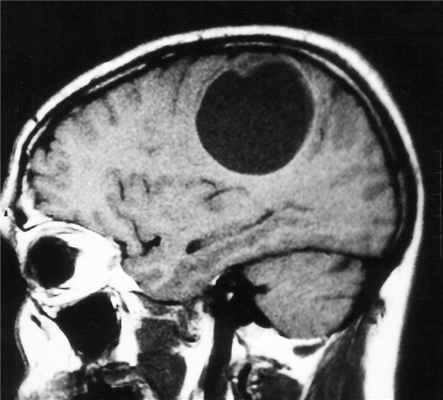

МРТ головного мозга. Астроцитома с большой реактивной кистой. Аксиальная Т2-зависимая и сагиттальная Т1-зависимая МРТ.